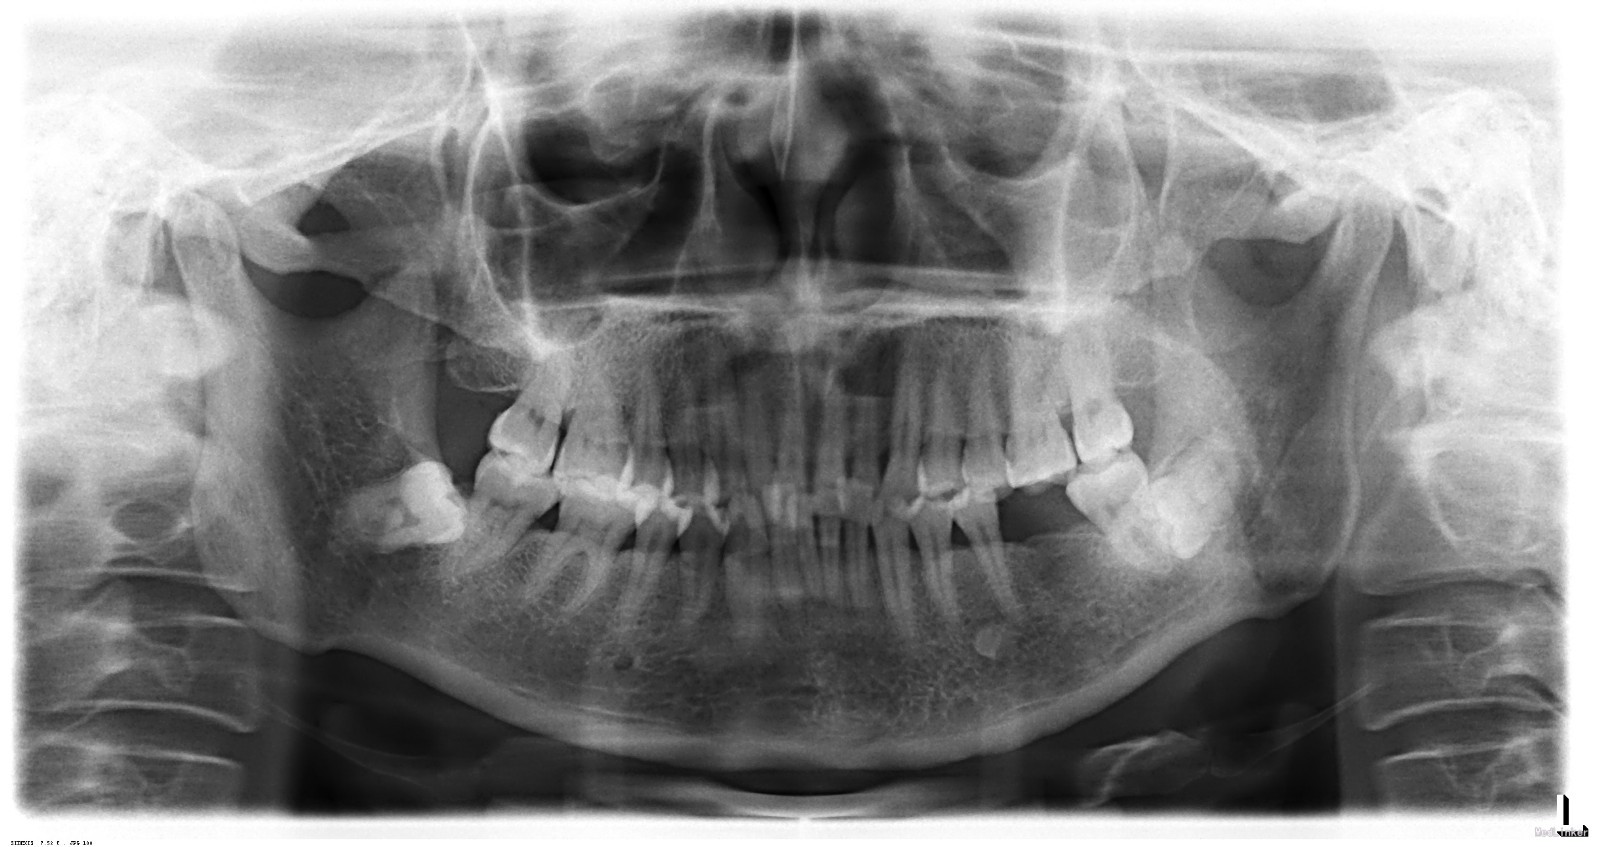

检查:口腔环境尚可,有轻微的牙结石覆盖于牙颈部位。48远中颊尖破龈萌出,冠周牙龈无急性炎性表现。

X线曲面体层片显示:48前倾低位埋伏阻生,牙冠近中部分嵌入47远中根部,48牙冠与47根部有明显线状透射影。诊断:48低位前倾阻生,47牙根吸收。

诊断:48低位前倾阻生,47牙根吸收。